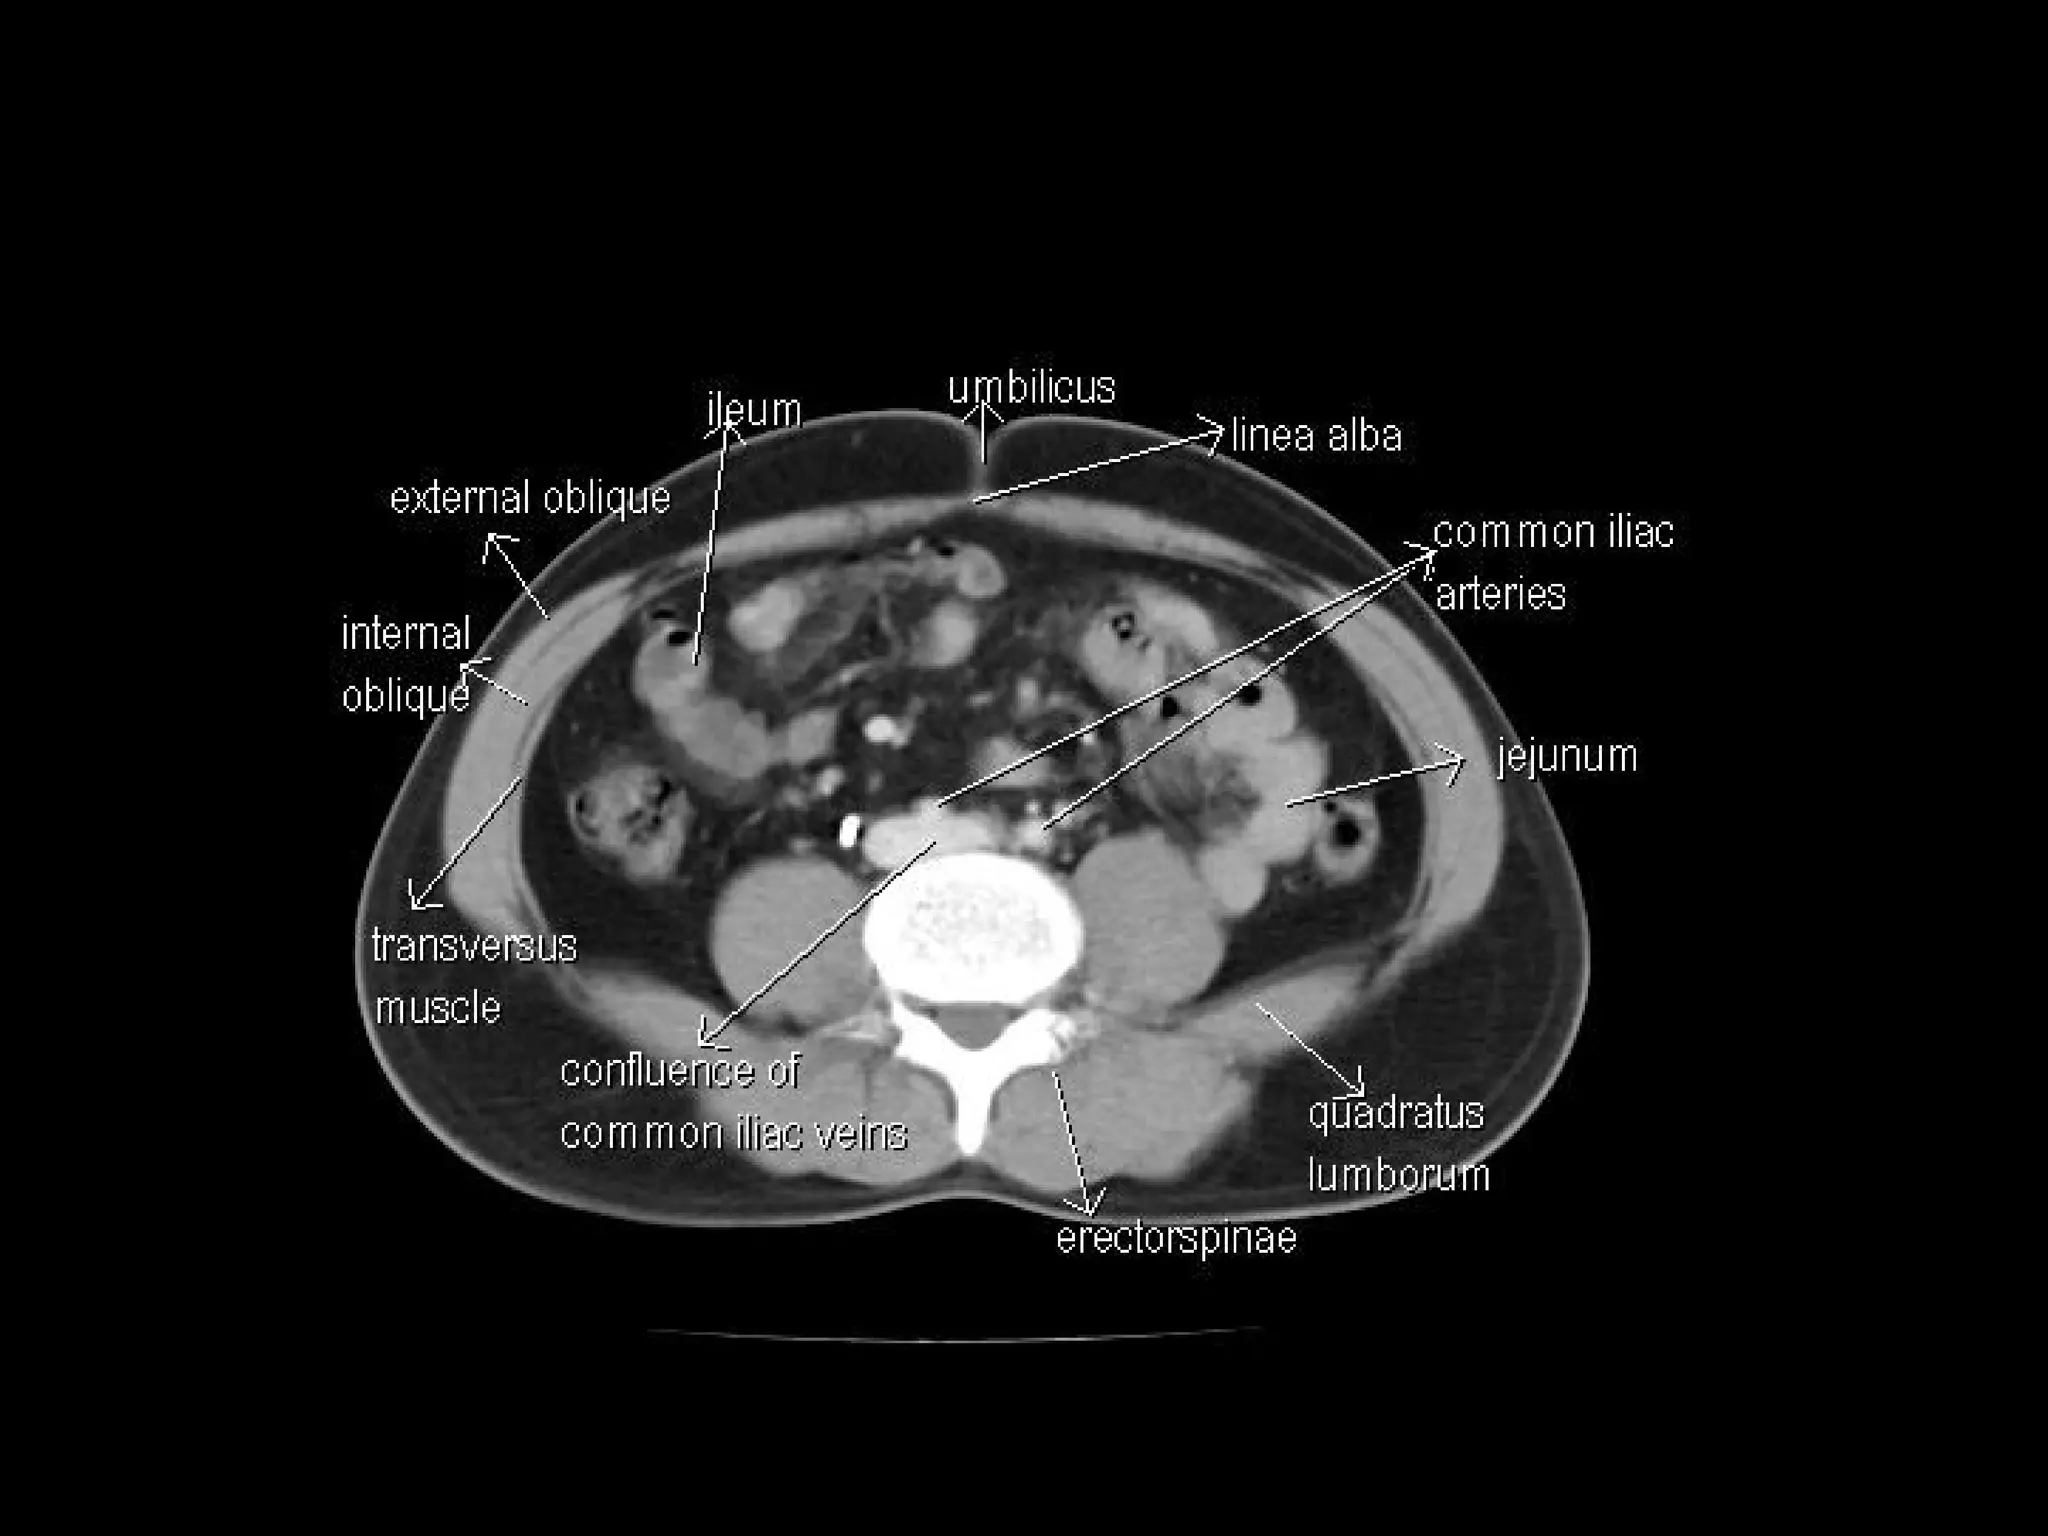

Radiographers are medical professionals who perform diagnostic imaging examinations and procedures to help physicians diagnose and treat diseases. They work under the supervision of radiologists to operate X-ray, CT, MRI, ultrasound and other medical imaging equipment and must have a strong understanding of human anatomy and pathology. Radiographers are responsible for correctly positioning patients, ensuring proper imaging techniques are used, and evaluating the quality of the resulting images.